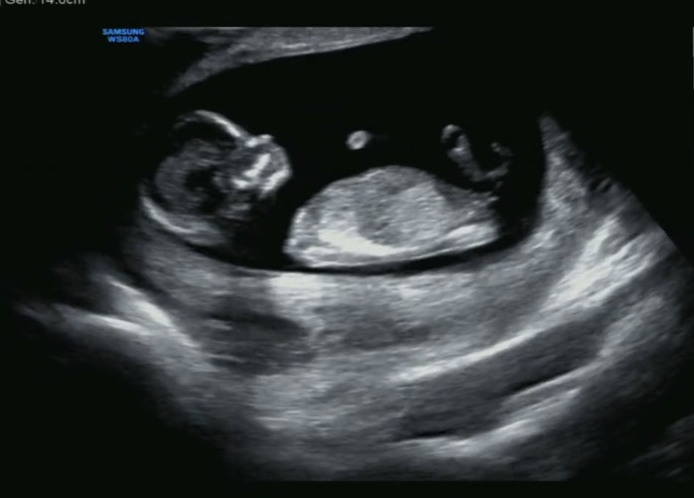

37주 4일, 응급 제왕절개 출산 후기 (양수과소증, 자궁 내 성장지연, 저체중아)

24주 차부터 꾸준히 작았던 우리 아이 열달후에 어플로 입력했을 때 허벅지 길이를 제외하고 모든 부분이 ...